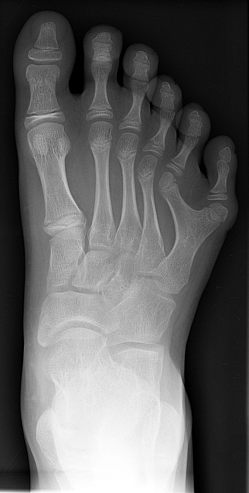

органов, дефекты поджелудочной железы. Как правило, наблюдаются полидактилия

(чаще двусторонняя и на руках) и флексорное положение кистей. Частота разных